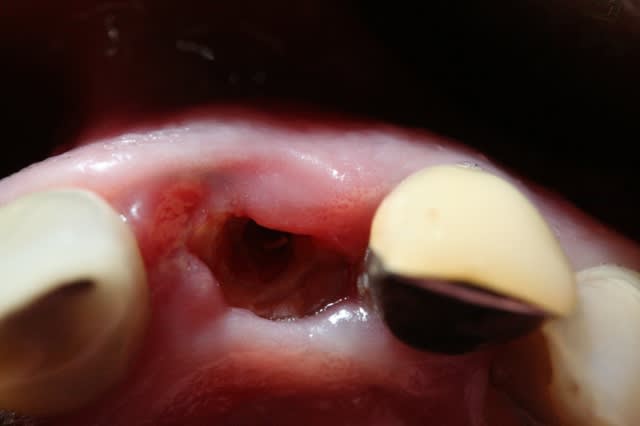

il y a selon moi perte de la table externe que j'estime à 2 mm de large et 3 à4 mm de haut.

je viens de revoir la patiente ce matin.

je commence à obtenir une gencive vestibulaire , ce qui me permettra de gérer la gencive plus facilement. je n'aurais donc peut être pas besoin de mettre la rustine que tu conseilles.

> Il semblerait que ton RTR s'est fait la malle :-(

oui, mais c'était parfaitement prévisible, je n'ai pas fermé l'avéole. peut être inutile à ce stade.

j'espère seulement garder un peu de volume là où il en reste.